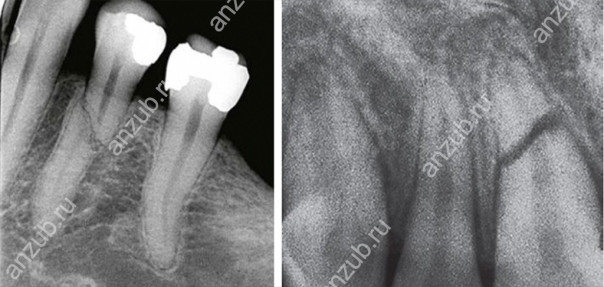

Наиболее информативным методом диагностики будет рентген или, лучше всего, компьютерная томография. С их помощью можно оценить не только место перелома и линию разлома, но и состояние окружающих тканей.